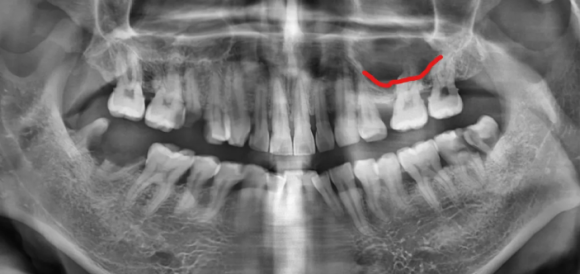

수술 후 변화

상악동 위치

안정적으로 이식된 인공뼈

왼쪽 위 어금니는 발치 후 골이식과 상악동 거상술을 함께 시행했습니다.

수술 후 엑스레이에서 상악동이 인공 뼈로 채워진 모습이 확인되었고, 임플란트가 안정적으로 자리 잡았습니다.

치료 전 24.02.13

치료 후 24.10.05

치료 후 환자분께서는 생각보다 회복이 빠르고 통증이 적었다고 좋아해 주셨습니다.